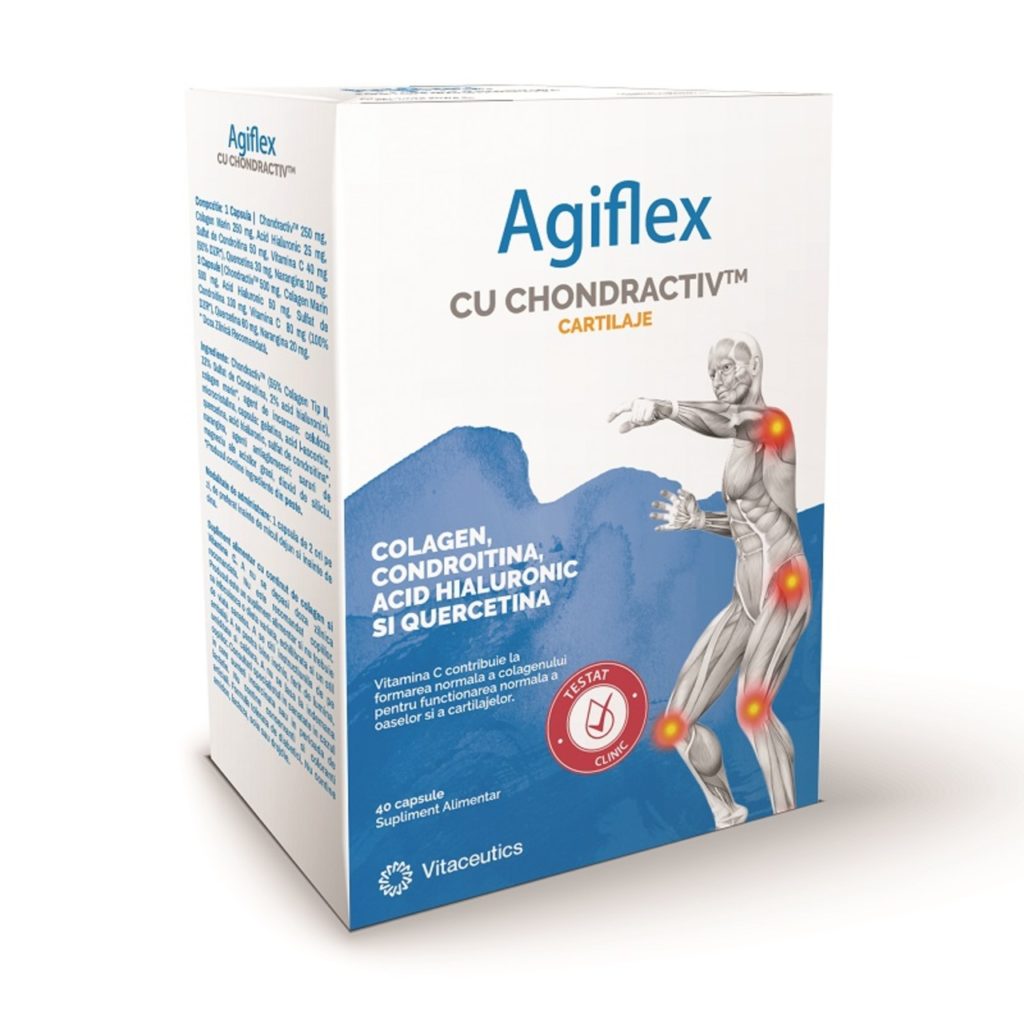

Agiflex – supliment complet pentru mobilitatea articulațiilor

Agiflex de la Vitaceutics este un supliment complet pentru mobilitatea articulațiilor. Combinația de colagen tip II, sulfat de condroitină, acid hialuronic și vitamina C sprijină refacerea lichidului sinovial și menținerea proprietăților vâscoelastice ale cartilajelor.

Suplimentul contribuie la mobilitate și flexibilitate, reducând riscul de accidentări și dureri articulare. Este perfect pentru sportivii care doresc să-și protejeze articulațiile în timpul antrenamentelor intensive sau al competițiilor, oferind nutrienții necesari pentru refacere și susținerea performanței.